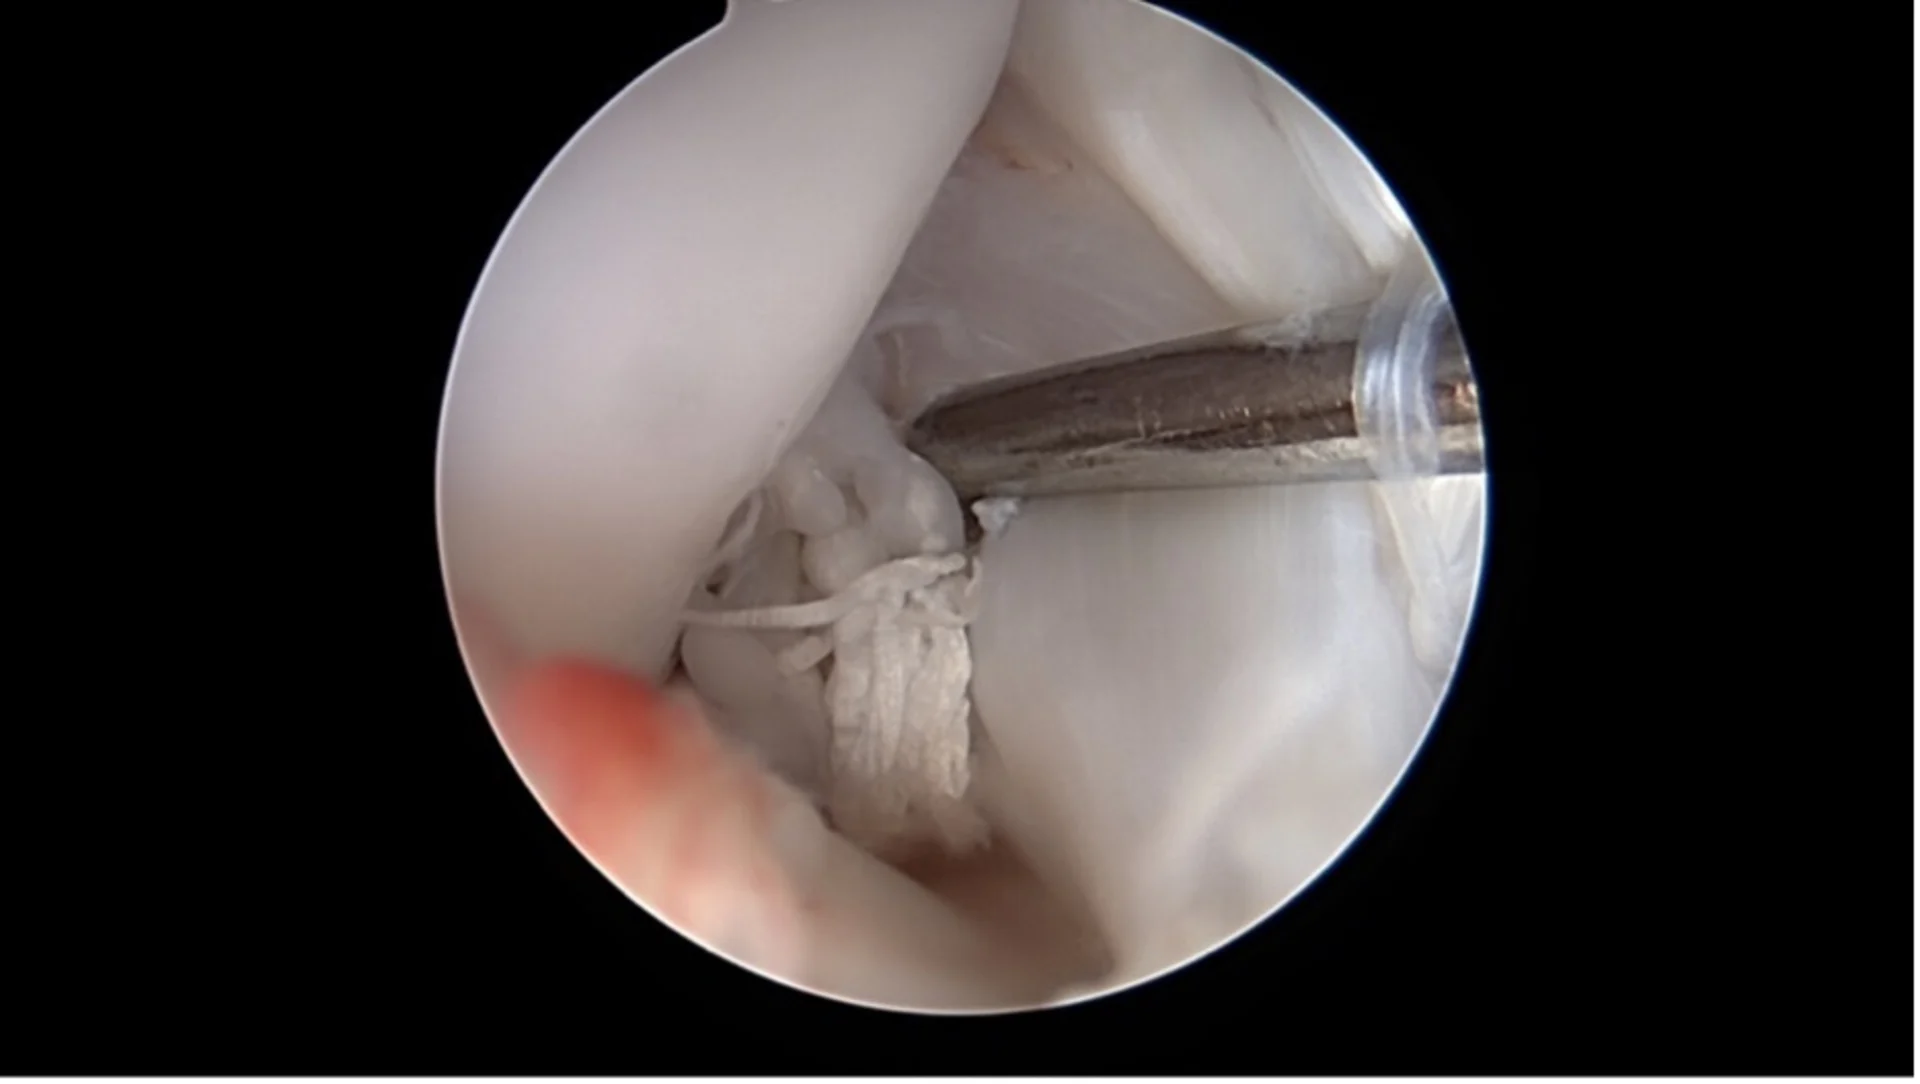

Arthroscopy

A miniature camera allows direct visualization of the inside of the joint through small skin incisions. Changes to the cruciate ligament and associated damage such as meniscal tears can be diagnosed and in many cases treated immediately.

Basket-handle meniscus tear